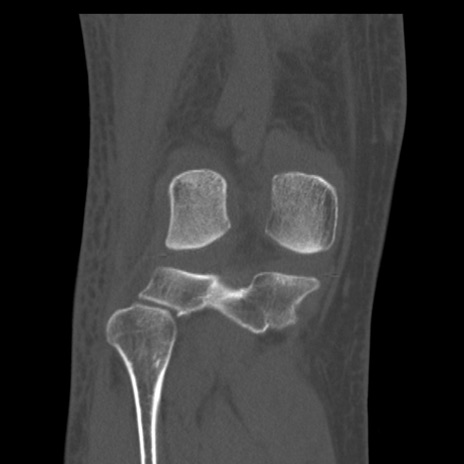

症例28 右膝関節CT(冠状断像)

右膝関節CT

横断像